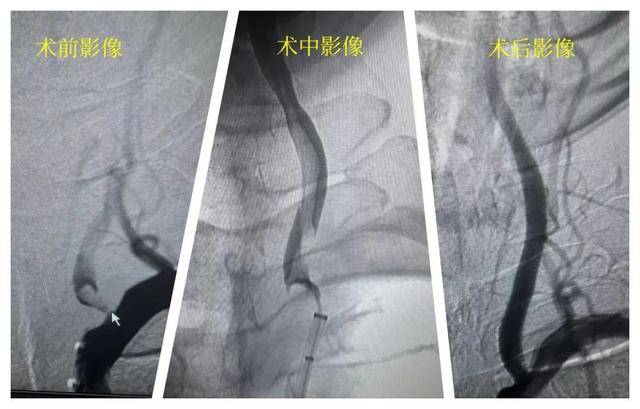

近日,62岁的张先生在家中突发右侧肢体无法活动、言语不清,家人立刻拨打急救电话,3小时内将其送达长沙市第一医院。急诊医生迅速安排了头部CT检查,排除了脑出血,进一步的血管造影检查(CTA)显示,供应大